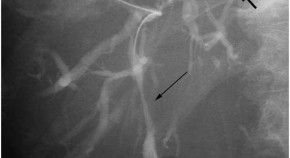

• This article highlights the case of a 74-year-old Caucasian female who presented with jaundice, clay-colored stools, diarrhea, and fatigue of 3 months' duration, accompanied by a weight loss of 6.8 kg. The results of initial investigations were interpreted as primary sclerosing cholangitis, but futher investigation revealed lytic and and blastic bone lesions. A sacral bone biopsy established the diagnosis of systemic mastocytosis.